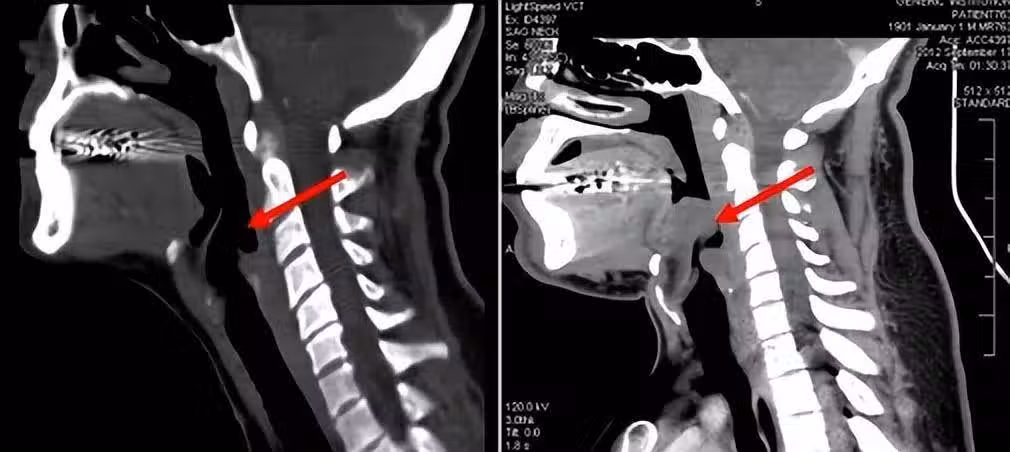

一般,急性會厭炎的病情進展十分迅速,一旦發病後沒有及時診療,可在極短時間內窒息,因此死亡率較高。